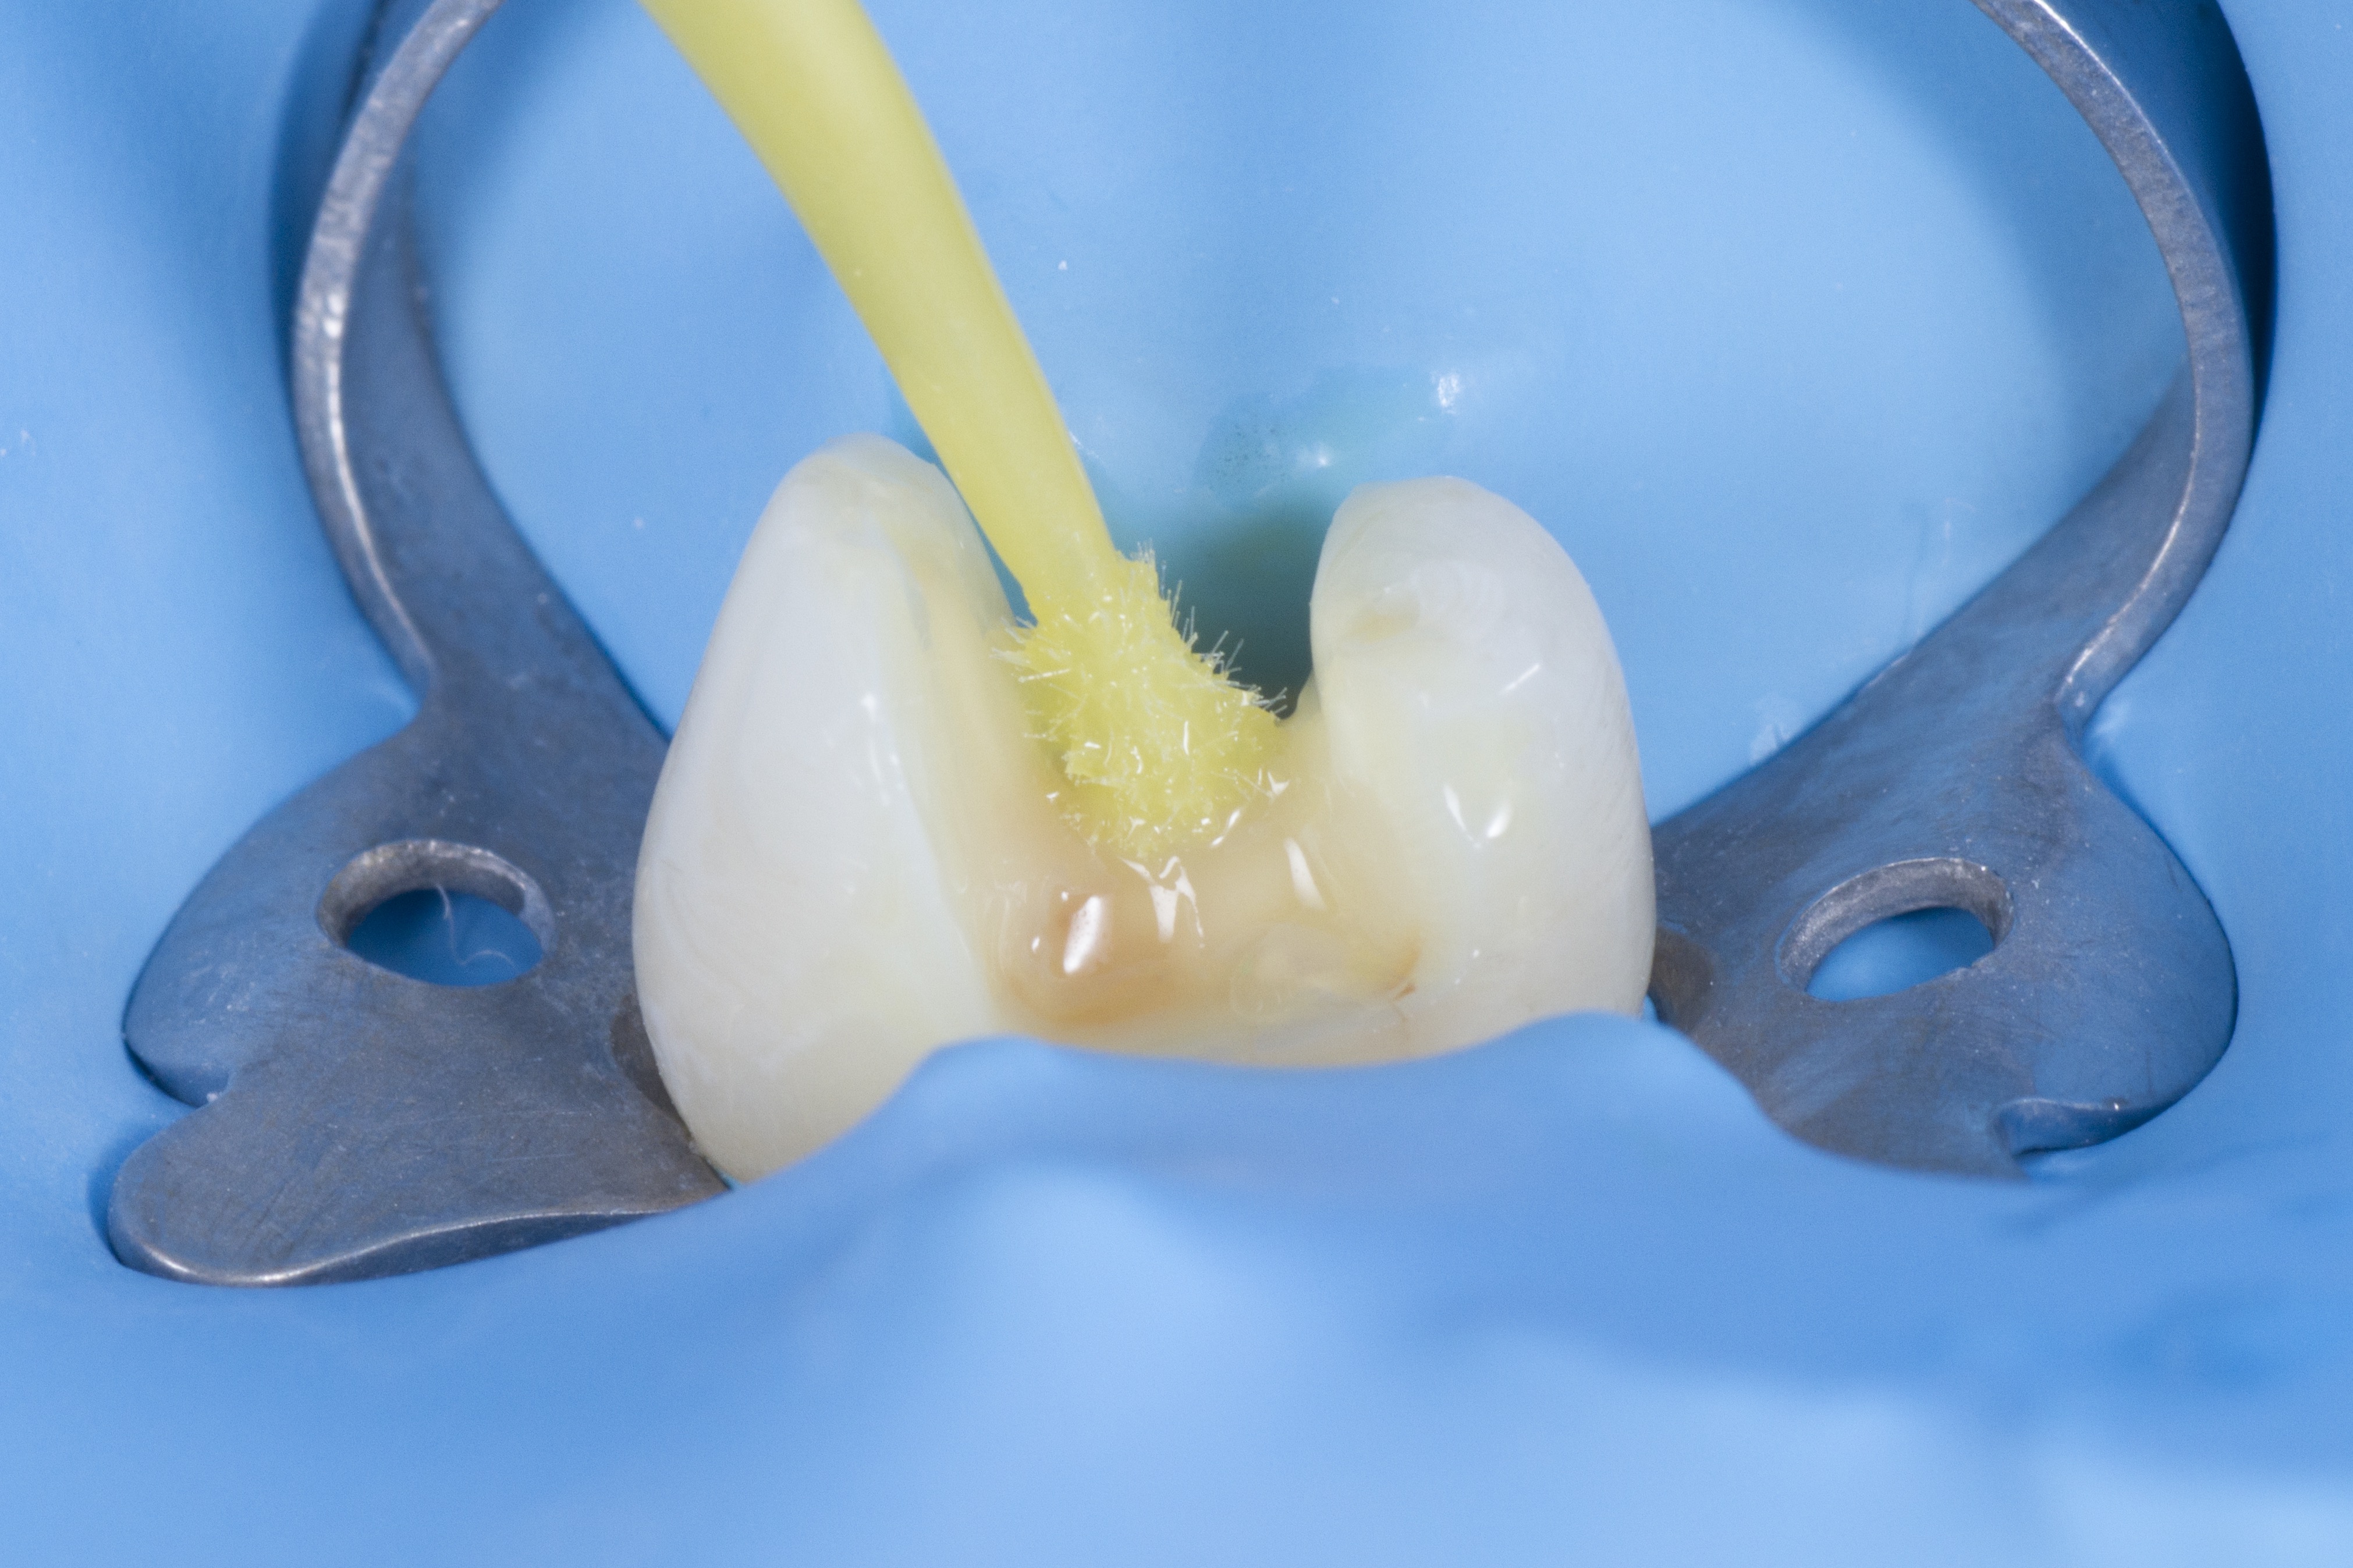

L’érosion-infiltration

Cette technique permet de faire disparaitre les taches blanches (et parfois brunes) sur les dents. Pour les plus superficielles d’entre elles, aucune instrumentation n’est nécessaire.

Avant-après :